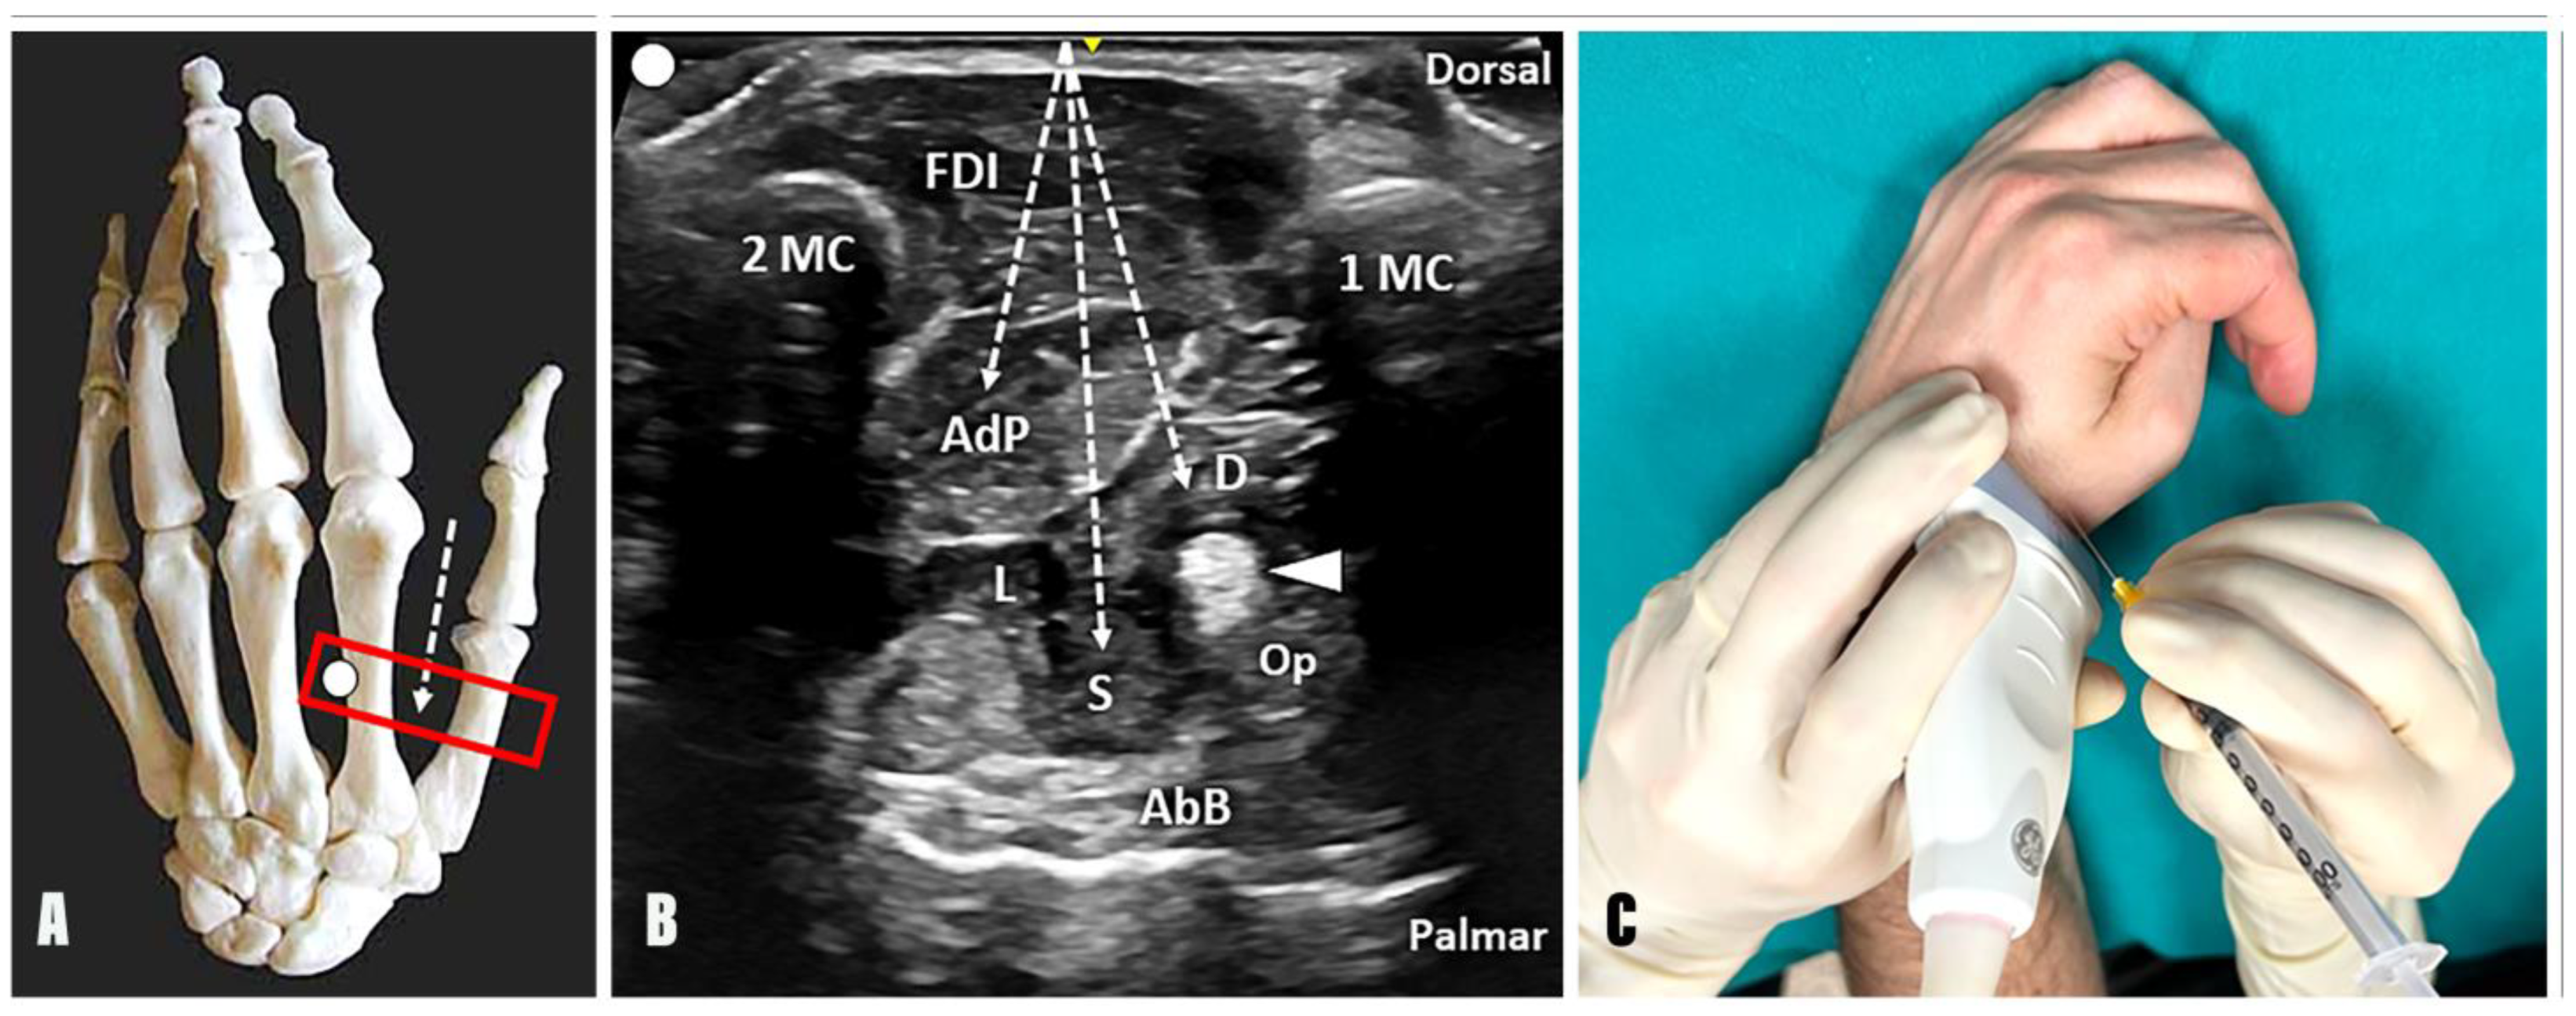

2.1.1. Adductor Pollicis Muscle

- Technique: Considering the second metacarpal bone as an anatomical landmark, the needle can be advanced using an out-of-plane technique and dorsal-to-palmar approach towards the AdP by crossing the FDI (Figure 2);

- Tips and tricks: The authors suggest slightly tilting the needle in an ulnar direction after the first inoculation point into the oblique muscle belly of the AdP and advancing towards the third metacarpal bone. At this level, a second inoculation can be performed to promote the diffusion of BTX towards the transverse muscular belly of the AdP as well. Of note, a small vascular bundle can be observed between the FDI, the AdP, and the second metacarpal bone using a transverse scan over the dorsal aspect of the first intermetacarpal space. In this sense, before the aforementioned ulnar tilting of the needle to reach and inject the transverse muscular belly of the AdP, a color Doppler assessment of this region should always be performed to ensure a safe interventional procedure (Supplementary Video S1).

- Technique: Considering the first metacarpal bone as an anatomical landmark, the needle can be advanced using an out-of-plane technique and dorsal-to-palmar approach toward the superficial and deep head of the FPB by crossing the FDI and the adductor pollicis muscle (Figure 2). Of note, using a dorsal approach, the deep head of the FPB is located between the AdP muscle and the FPL tendon; instead, its superficial head can be identified between the FPL tendon and the abductor pollicis brevis (AbB) muscle. In this sense, an excessive advancement of the needle in a palmar direction may be associated with an unintentional release of BTX into the AbB muscle.

- Tips and Tricks: A distal to proximal sonographic tracking of the flexor pollicis brevis may assist in differentiating its two muscular heads. Indeed, the superficial head originates from the flexor retinaculum and the tubercle of the trapezium bone; conversely, the deep head originates more medially from the trapezoid and capitate bones. When using this acoustic window in patients with a “thumb-in-palm” hand deformity, the Op muscle can be identified, in some rare cases, between the FPL tendon and the AbB muscle on the radial side (Figure 1). More commonly, the Op muscle is extremely difficult to recognize, and an unintentional spilling of BTX in the muscle may occur, without compromising the effective release of the thumb flexion [12].